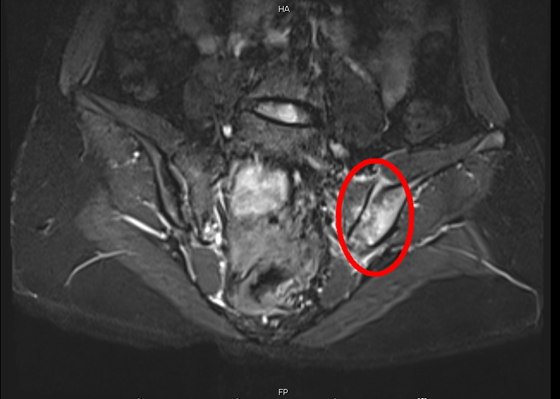

今年17岁的小龚,最近感觉屁股越来越疼,连走路都疼,于是她在父母的陪同下来到湘雅常德医院求医。经了解,小龚4年前开始出现屁股痛的情况,刚开始是右边屁股痛,早晚会厉害些,站起来走...